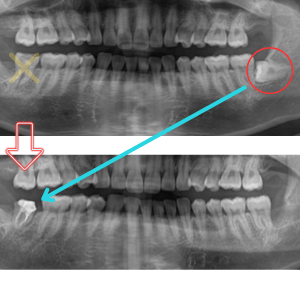

当院で抜歯できない親知らずは骨の中を通っている下歯槽神経と親知らずの根の部分が明らかに接しているケースです。CT撮影を行い、神経と接しているケースは大学病院などの口腔外科へ紹介致します。

下の親知らずの根の先は下歯槽神経という神経に近接しています。場合によっては神経と親知らずの根の先が触れているケースがあり、親知らずの抜歯の際に親知らずが揺らされる事によりこの神経を圧迫してしまったり、傷つけてしまう事で、唇にしびれが残ってしまうケースがございます。CT撮影を行い、下歯槽神経と親知らずの根が近接している場合はリスクを考慮したうえで、高次医療機関への受診をすすめる場合もあります。

横にはえて大部分が歯肉の下に埋まっている下の親知らずを安全に抜歯するためにCTを撮影し下歯槽神経との関係を調べた後に抜歯した場合、3割負担で8000円程度です。